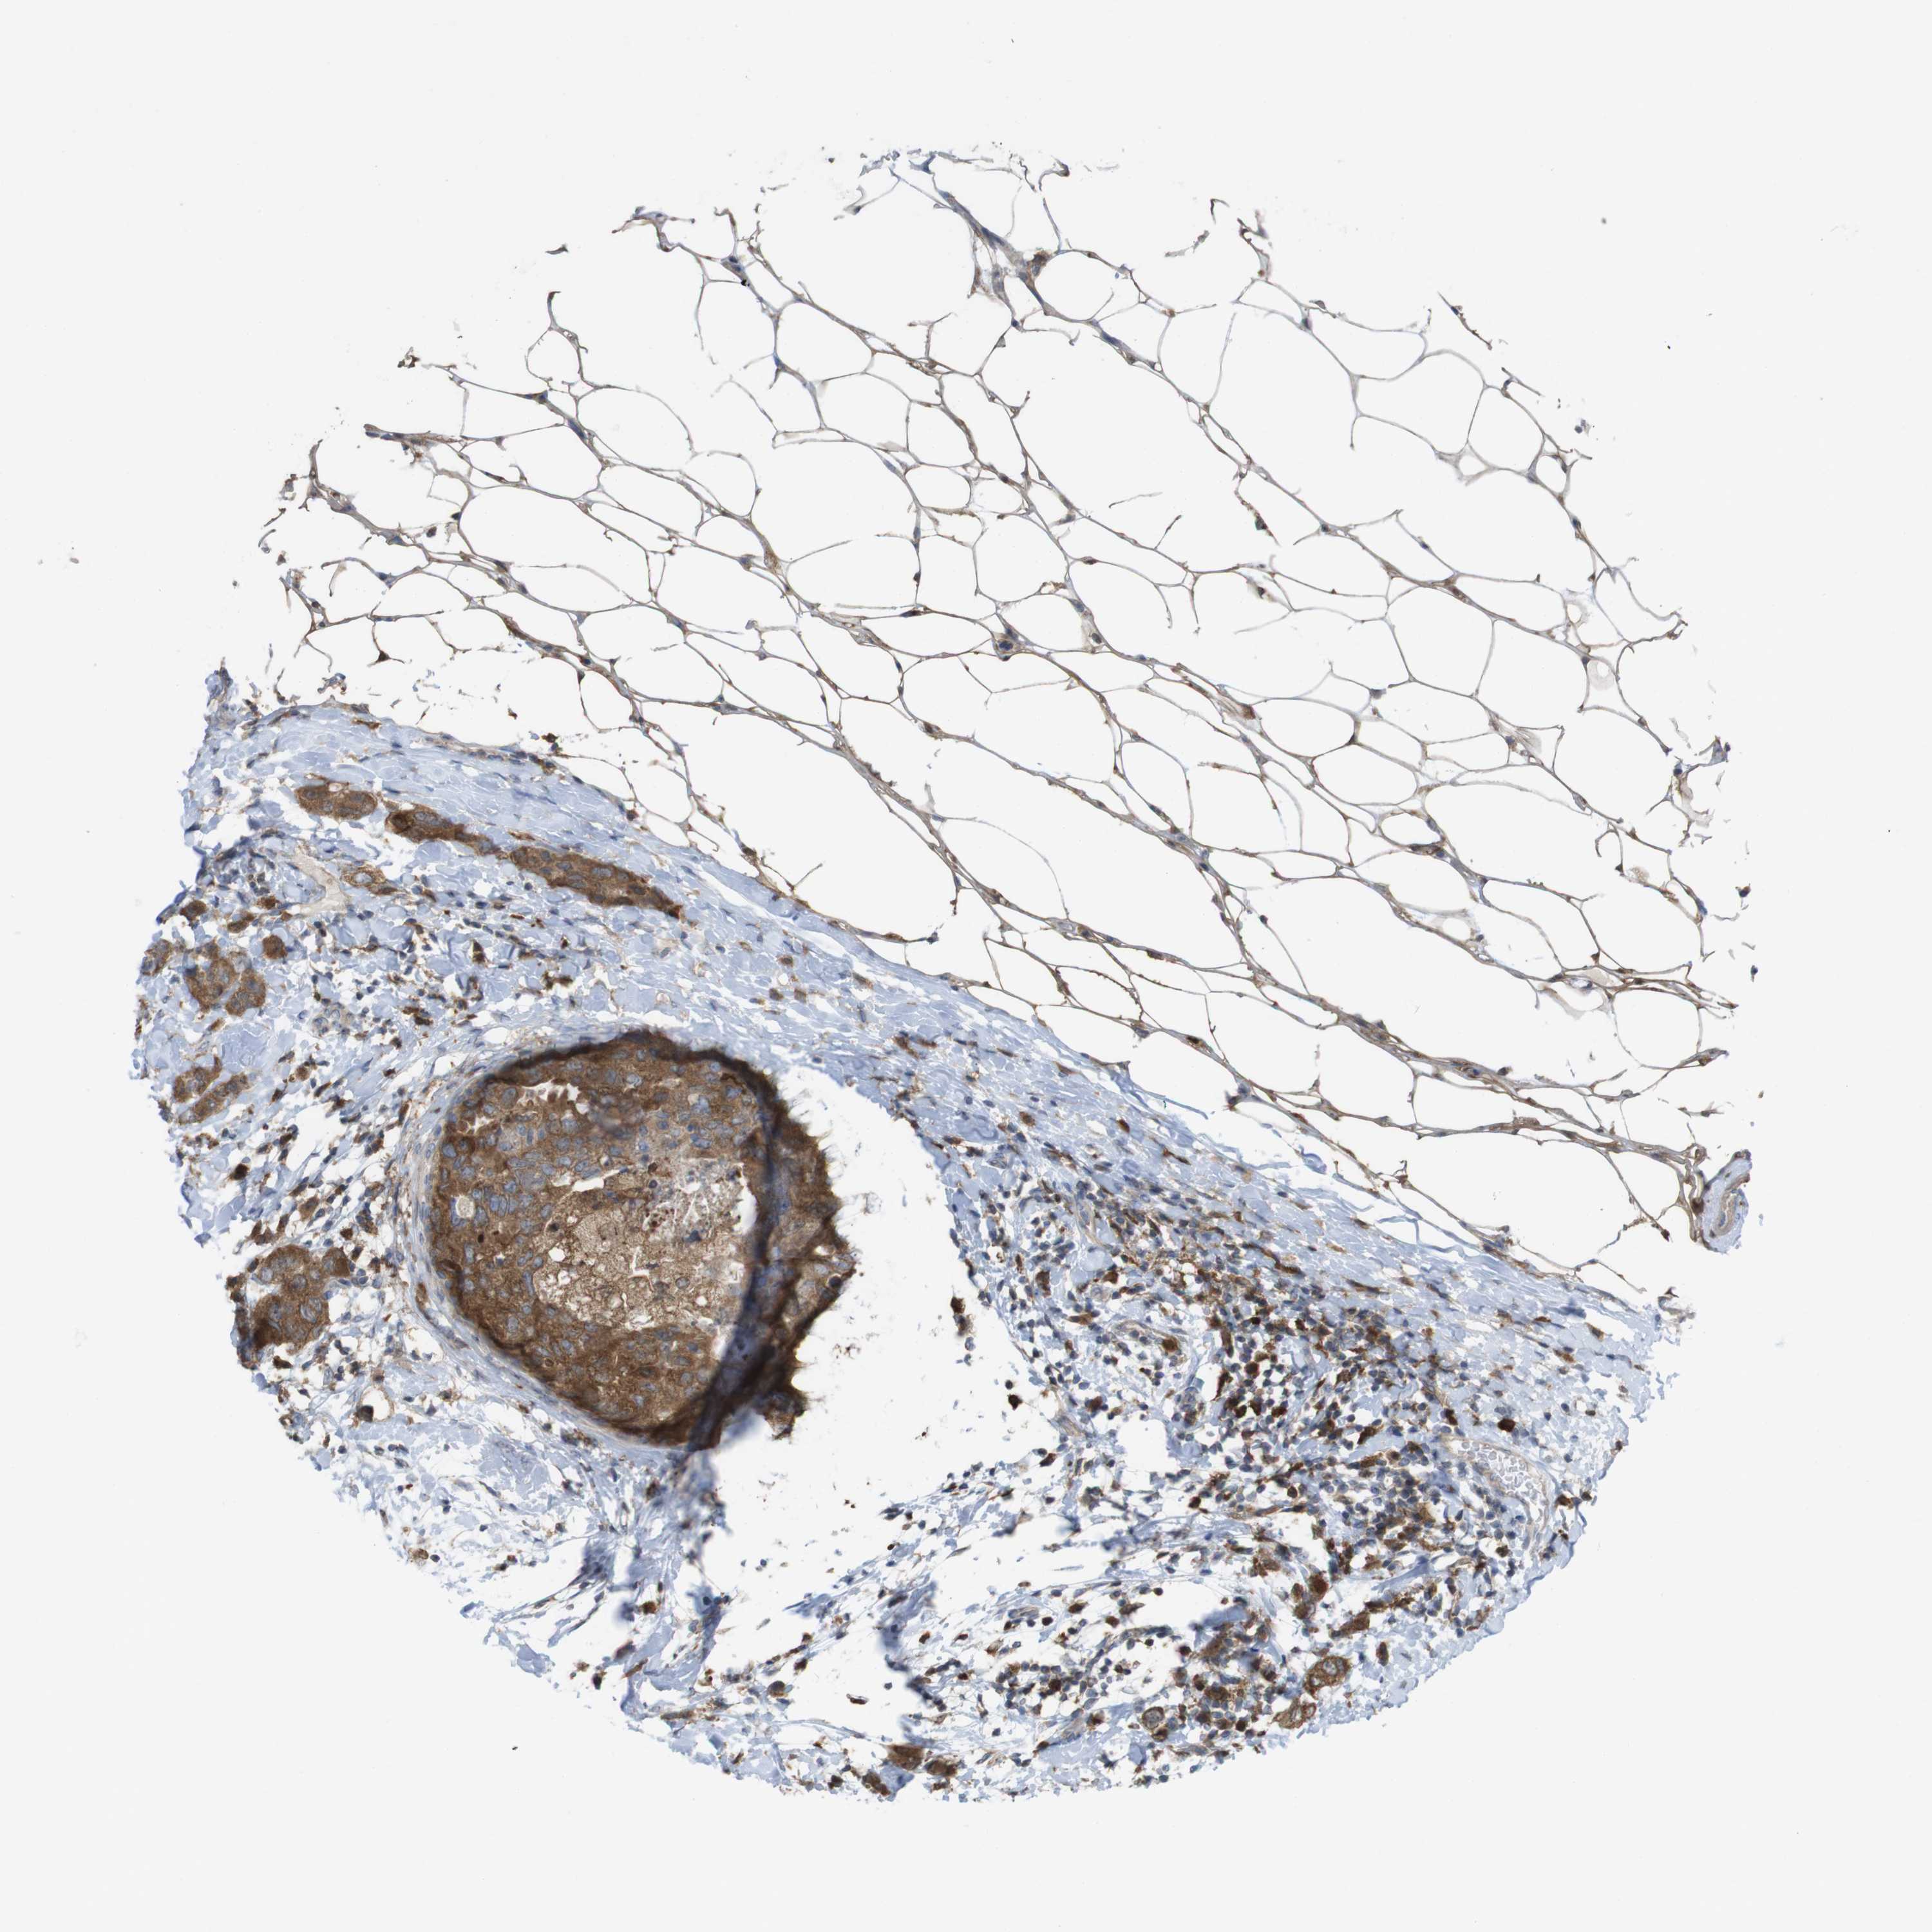

BRCA TCGA BRCA VALIDATION PROTEIN EXPRESSION